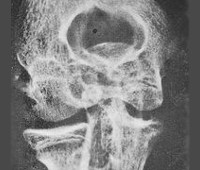

• Инструментальные исследования. При рентгенографии сустава определяются следующие симптомы - отек синовиальной оболочки и околосуставных тканей, сужение суставного пространства, краевая эрозия и остеопороз, остеомиелит, зоны секвестрации, кальцификация периартикулярных тканей. В сомнительных случаях выполняются магнитно-резонансные и расчетные изображения, которые являются более чувствительными.